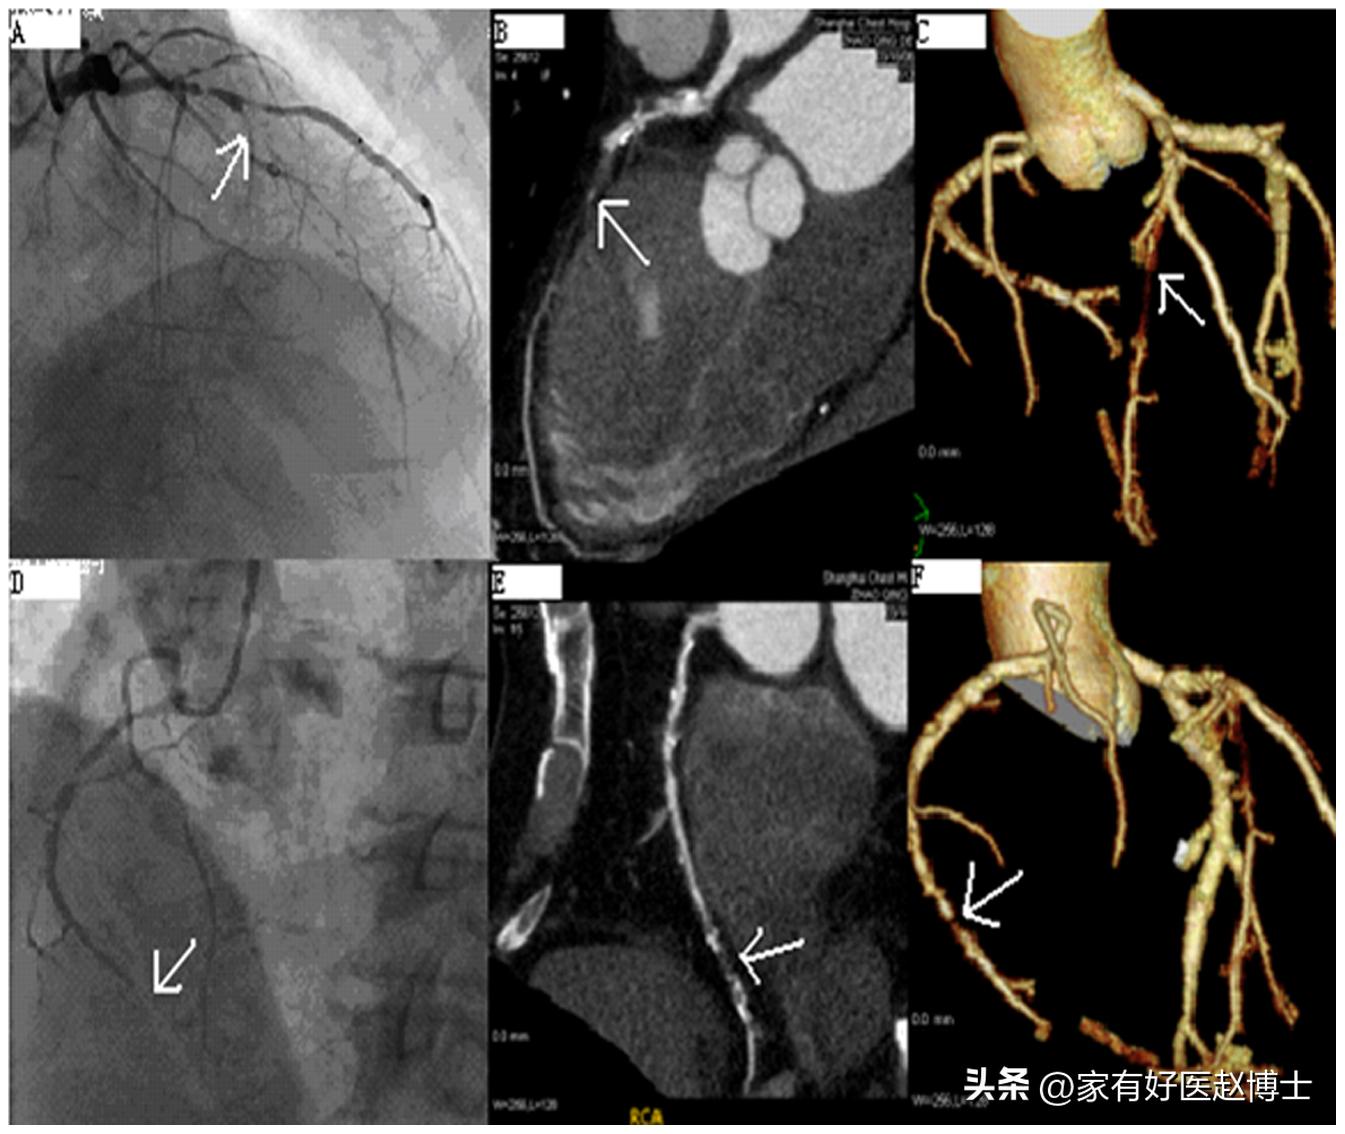

目前,临床上最常用于“看”冠状动脉的检查有两个:一个是“冠脉造影”;还有一个则是“冠脉CTA”。

冠脉CTA不需要进行动脉穿刺,也不需要往身体里放入长长的导管,整个检查过程类似于一次增强的CT检查,且总体费用低于冠脉造影。因此,害怕冠脉造影的患者,往往更容易接受冠脉CTA检查。

而假如,除了“冠脉钙化”以外,体检当中还发现心电图有心肌缺血的征象,血压、血脂、血糖等指标有明显异常,并且,经常发生胸痛、胸闷等症状的话,那就有必要做冠脉CTA看一看了。甚至,有时候医生会建议直接做冠脉造影检查!